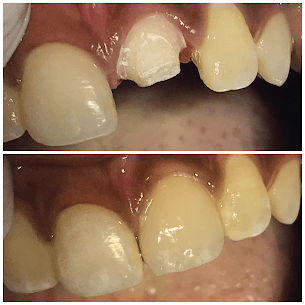

Emergency Composite Repair

Single-visit composite restoration for 27-year-old male with chipped tooth